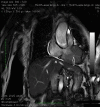

Metastatic spread to the heart from neoplasms is very rare, often silent and rarely gains clinical attention. Usually, it correlates with widespread metastatic disease and is suggestive of a poor prognosis. Most cardiac metastases (CM) are detected following post-mortem studies with only a handful reported antemortemly. Here, we report a case of an asymptomatic cardiac metastasis from esophageal carcinoma and a review of the literature. In late July 2014, a 73-year-old woman diagnosed with locally advanced esophageal squamous cell carcinoma was admitted to our institution. Cardiothoracic metastases were not detected at basal computed tomography (CT) scan. The patient was submitted to concurrent cisplatin and radiotherapy. Just before surgery, a CT scan revealed two metastases in the right ventricle and in the interventricular septum. Transthoracic echocardiography and an endomyocardial biopsy confirmed the diagnosis of squamous cell carcinoma from the esophageal origin. In February 2015, chemotherapy was started, but after two courses of gemcitabine, a pulmonary embolism and then a congestive heart failure caused death of the patient on April 2015. Reviewing the literature, 14 cases with an antemortem diagnosis of CM from esophageal cancer were reported. Our patient should be the fifteenth case with an uncommon presentation without symptoms or signs in the diagnosis. Our case highlights that patients should be evaluated using echocardiography for CM, even if asymptomatic.